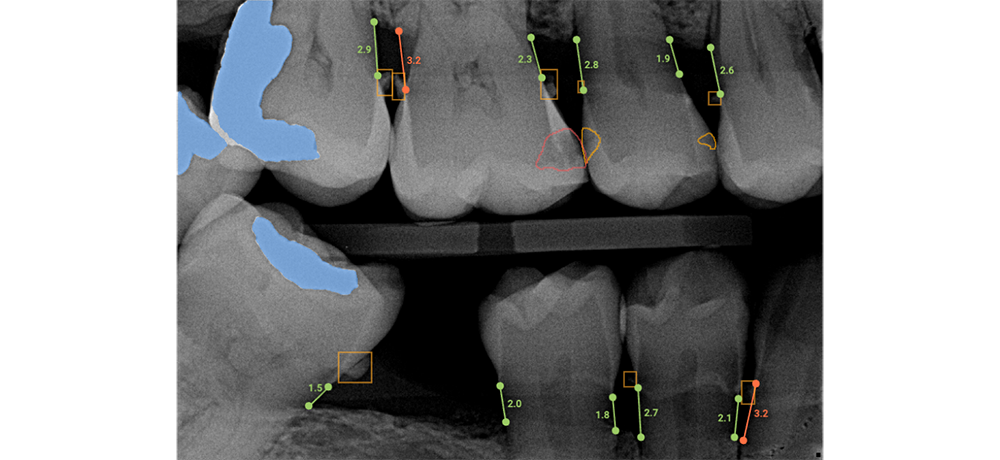

Caries Assist, an FDA-cleared artificial intelligence (AI)-powered dental caries detection and outlining software

This technology is applied in real-time to periapical radiographs and bitewing radiographs for patients 12 years and older with permanent teeth.

Overjet Caries Assist enables clinicians to detect caries, reduce the rate of false negatives (missed lesions), and enhance patient education through visualization. In an analysis of 7,000 tooth surfaces, Overjet Caries Assist helped dentists detect 32% more tooth surfaces containing caries, according to an Overjet study.

Overjet enables dentists to be more effective and efficient by providing an AI-generated analysis of dental radiographs to help with their clinical decision-making and case presentation. Overjet is the only dental AI company that is FDA-cleared to detect and outline decay, detect calculus, and quantify bone level measurements. The AI findings provide instant visualizations, which improve patient communication, elevate patient understanding of their oral health conditions, and support better patient outcomes.